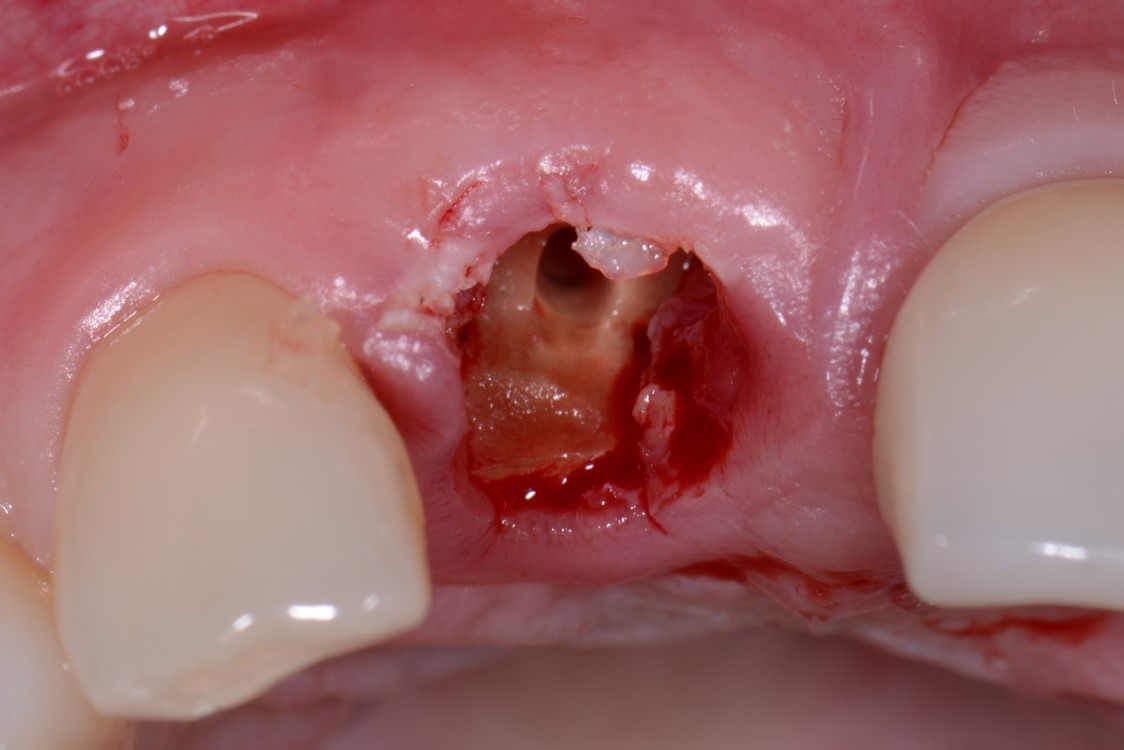

Fig 8. Case 1: A patient presented in January 2006 with a large periapical lesion, a root fracture, and significant buccal bone loss.

Figure 8

Fig 9. Despite the extent of bone loss revealed radiographically, multiple surgical grafting procedures were not indicated. Instead, a flapless surgery would be performed and biologic innovations used to facilitate ridge preservation.

Figure 9

Fig 10. The tooth was extracted; the socket debrided and degranulated; and ridge preservation was performed with FDBA/rhPDGF and an absorbable membrane.

Figure 10

A patient presented with a large periapical lesion, root fracture, and significant loss of buccal bone (Figure 8 and Figure 9). Treatment for this case involved an autogenous bone graft, then implant placement and connective tissue grafting. Recombinant human platelet-derived growth factor-BB was used for ridge preservation and minimally invasive esthetic implant site development with a flapless approach.

The tooth was extracted, and magnification was used while debriding and degranulating the extraction socket. The site was irrigated with a significant amount of sterile water from 10-mL syringes, and the water pressure helped with debridement. Spoon and #4 Gracey curettes were used.

Once degranulated and debrided, the growth factor matrix (eg, freeze-dried bone allograft that was presoaked in rh-PDGF-BB for about 10 minutes) was condensed into the site. The site was then covered with a collagen membrane and sutured.

After healing, the site was evaluated and a high frenum attachment was observed (Figure 10). A frenectomy was performed prior to implant placement, along with a connective tissue graft to thicken the soft tissues.